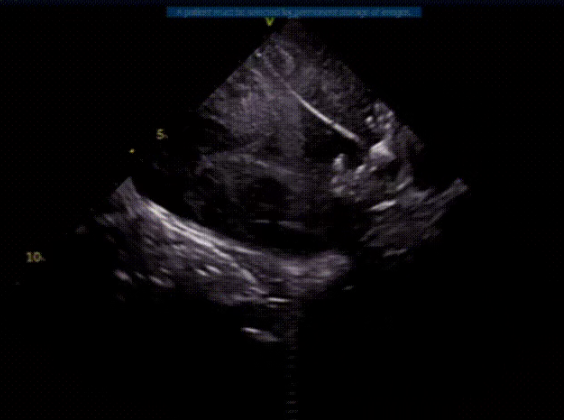

ICE扫描心耳评估血栓位置

渐进式将血栓推行远端

面对左心耳口部存在不稳定血栓这一核心难点,心血管内二科迅速联合神经内科、介入医学科等多学科专家进行深入评估。为最大程度确保治疗安全,团队最终确定了结合心腔内超声引导与“脑保护装置下带栓封堵”的个体化手术方案,为手术提供了至关重要的“双重保险”。

术中,治疗团队在心腔内超声和脑保护装置的全程守护下,精准处理了血栓,并成功释放封堵器。术后即时评估显示,治疗达到了预期目标——将血栓完全封堵左心耳内,且术中未发生任何血栓脱落并发症。手术取得成功!